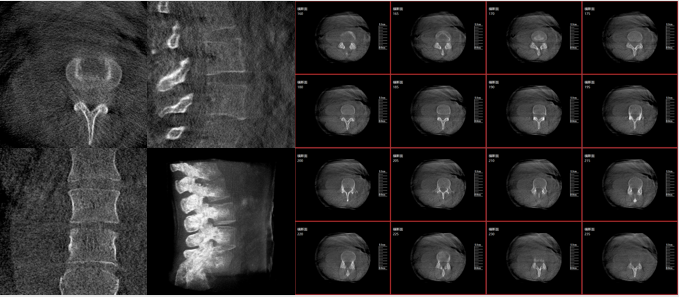

术中三维影像

而三维影像的MPR图像组可以通过不同平面的切分,使成像区内更丰富的信息得以呈现。尤其是二维影像无法涉及的横断面,提供了另一个空间维度的信息量。

作为使用者,医生在手术中虽然有术前的影像作为判定依据,但每一台手术都具有独特性,需要术中三维影像提供的实时信息,作为术中诊疗操作的基础。

在MPR图像中,冠状面、矢状面和横断面的信息大大提高了医生对于病灶区以及手术效果的判定。